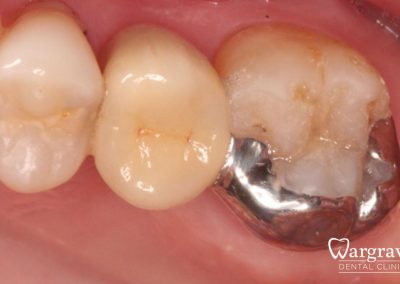

Healthy Smiles These are more advanced examples of different treatments available.All cases shown were carried out by Dr R Khurana unless otherwise stated. Immediate implants Anterior Mandible Bone Regeneration Anterior Mandibular Implant Bridge Maxillary Anterior Implant Bridge Implant stabilised ‘Life Like’ replacement dentures Implant Bridge after 10-years with zero bone loss Implant examples including ZBLC concepts Adhesive Bridge solution for a missing premolar Multidisciplinary care Orthodontics, Replacement veneers and composite bonding Adhesive Bridge solution for missing central incisors Replacement crown, Veneer and Composite Bonding Replacement Crowns and Veneer Injection Moulding using Composite Resin Equilibration Tooth Whitening to treat Developmental Discolouration